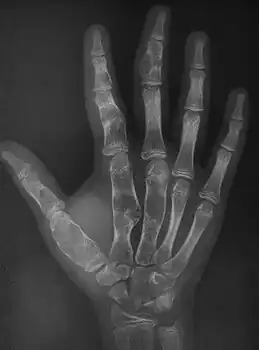

X-ray hand:Ollier disease in child